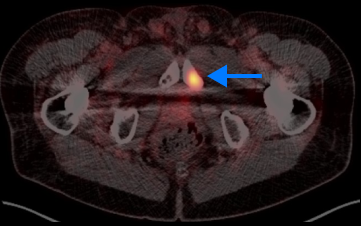

High-risk patient with newly diagnosed prostate cancer

Age

72

PSA (ng/mL)

5.1

Gleason Score

4 + 4

PYLARIFY prompted treatment change from prostatectomy to systemic therapy, thereby avoiding undertreatment